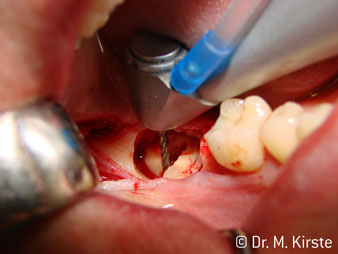

Die Winkelwahl des 45° Handstücks bringt viele Vorteile in der Anwendung. Chirurgisch tätige Kollegen, und für diese ist das Handstück in erster Linie entwickelt worden, werden schnell bemerken, dass man sehr gezielt arbeiten kann. Insbesondere bei der Weisheitszahnentfernung (Abb. 2) bedarf es keiner großen Weichteilabspreizungen im Wangenbereich (Abb. 3). Die Handstückkopfgestaltung kombiniert mit leichten Kopfdrehungen bei der Präparation lassen ein sicheres und schnelles Arbeiten im retromolaren Bereich zu.

Die professionelle Lagergestaltung im Innenleben des Handstückkopfes garantiert einen ruhigen Lauf der Bohrer, bei der Zahn- oder Wurzelseparation (Abb. 4 - 9) zeigt sich ein beeindruckendes Schnittbild ohne Schlageffekte.

Das 45 ° Winkelstück liegt sehr gut in der Hand. Man bemerkt sehr schnell, dass der Arbeitskopf dem Winkel des Zeigefingers nachempfunden und somit die gewünschte Bewegung nur einige gedachte Zentimeter parallel an die Spitze verschoben ist. (Abb. 1)“